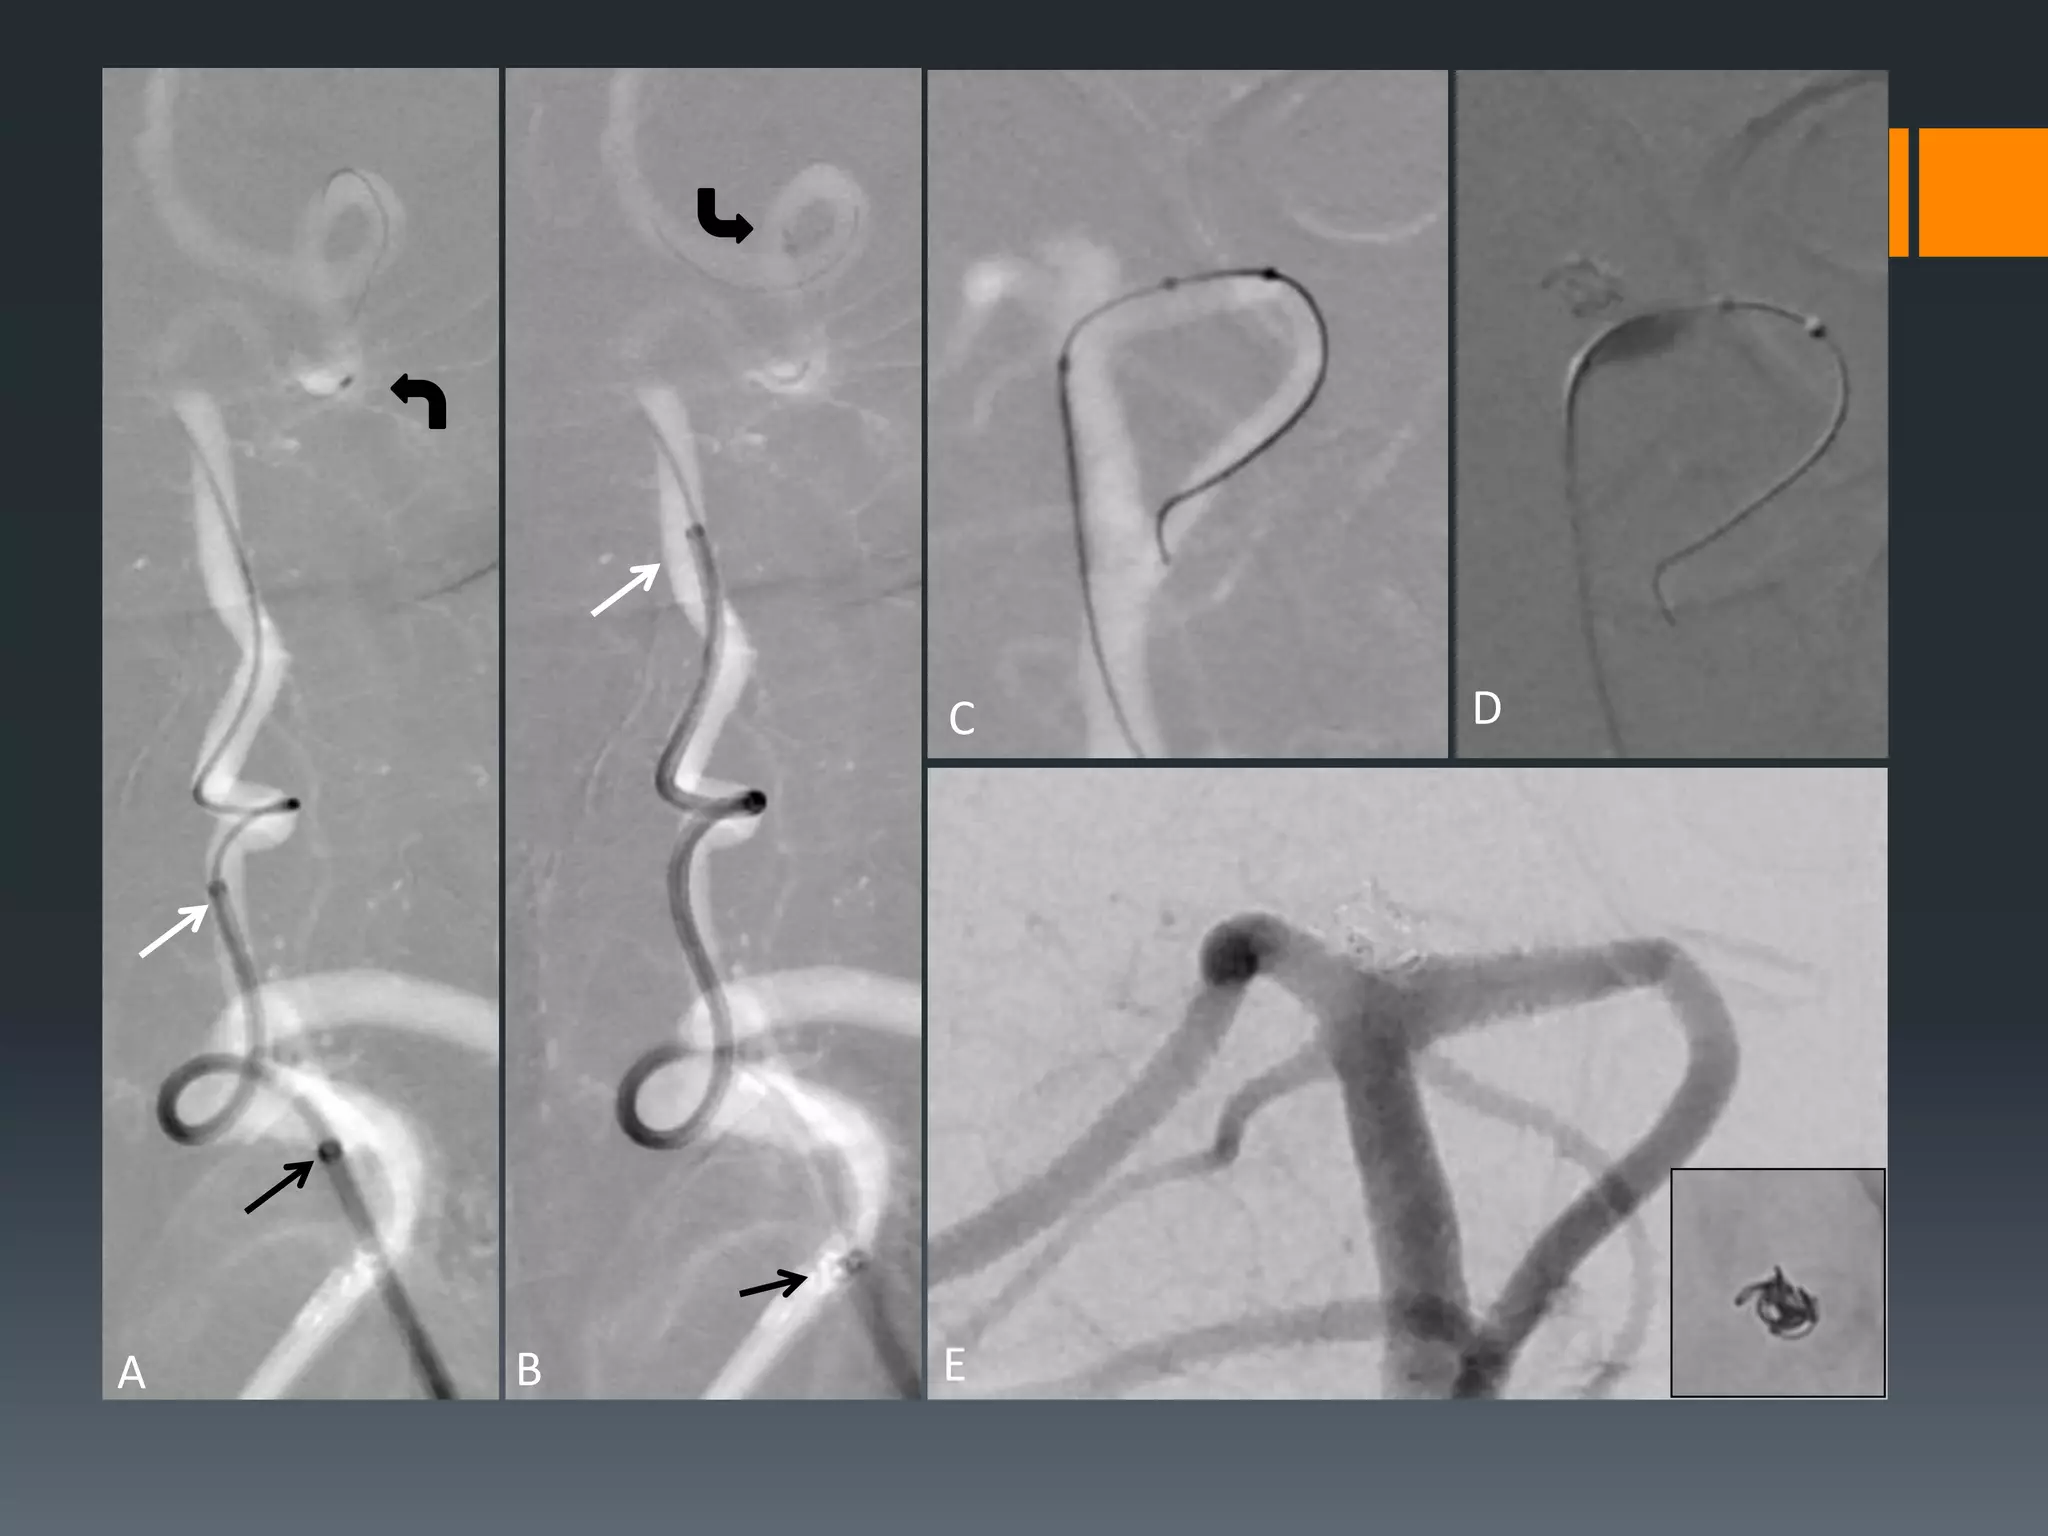

This document discusses tricks and techniques for difficult cannulations during neurointerventional procedures. It outlines strategies for accessing the aortic arch, internal carotid artery (ICA), and areas distal to aneurysms. Long sheaths, distal access catheters, and co-axial techniques are presented as options that have improved cannulation success. Guidance on sheath and catheter selection is provided for different vessel paths. The importance of catheter placement as high as possible in the ICA is emphasized. Reverse curve cannulations are also mentioned. Overall, the document stresses that careful cannulation is critical for procedural success and different strategies may be needed depending on the vessel target.